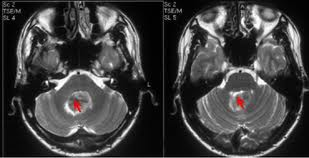

El TAC, prueba radiológica de elección para el diagnóstico demuestra las lesiones intracraneales asociadas a traumatismo craneoencefálico (TCE).

Los traumatismos craneoencefálicos, suponen una causa importante de morbimortalidad en jóvenes. Son muy importantes en Atención Primaria, considerándose la causa más frecuente de epilepsia en adolescente y adultos jóvenes, y es la primera causa de pérdida de conciencia de instauración brusca. Analizaremos los diversos traumatismos craneoencefálicos: fracturas de cráneo, conmoción, contusión, cizallamiento, hemorragias cerebrales, lesión axonal difusa, hematoma subdural y hematoma epidural. Para su valoración se utiliza la escala de Glasgow. El TAC, prueba radiológica asociada para analizar las lesiones intracraneales.